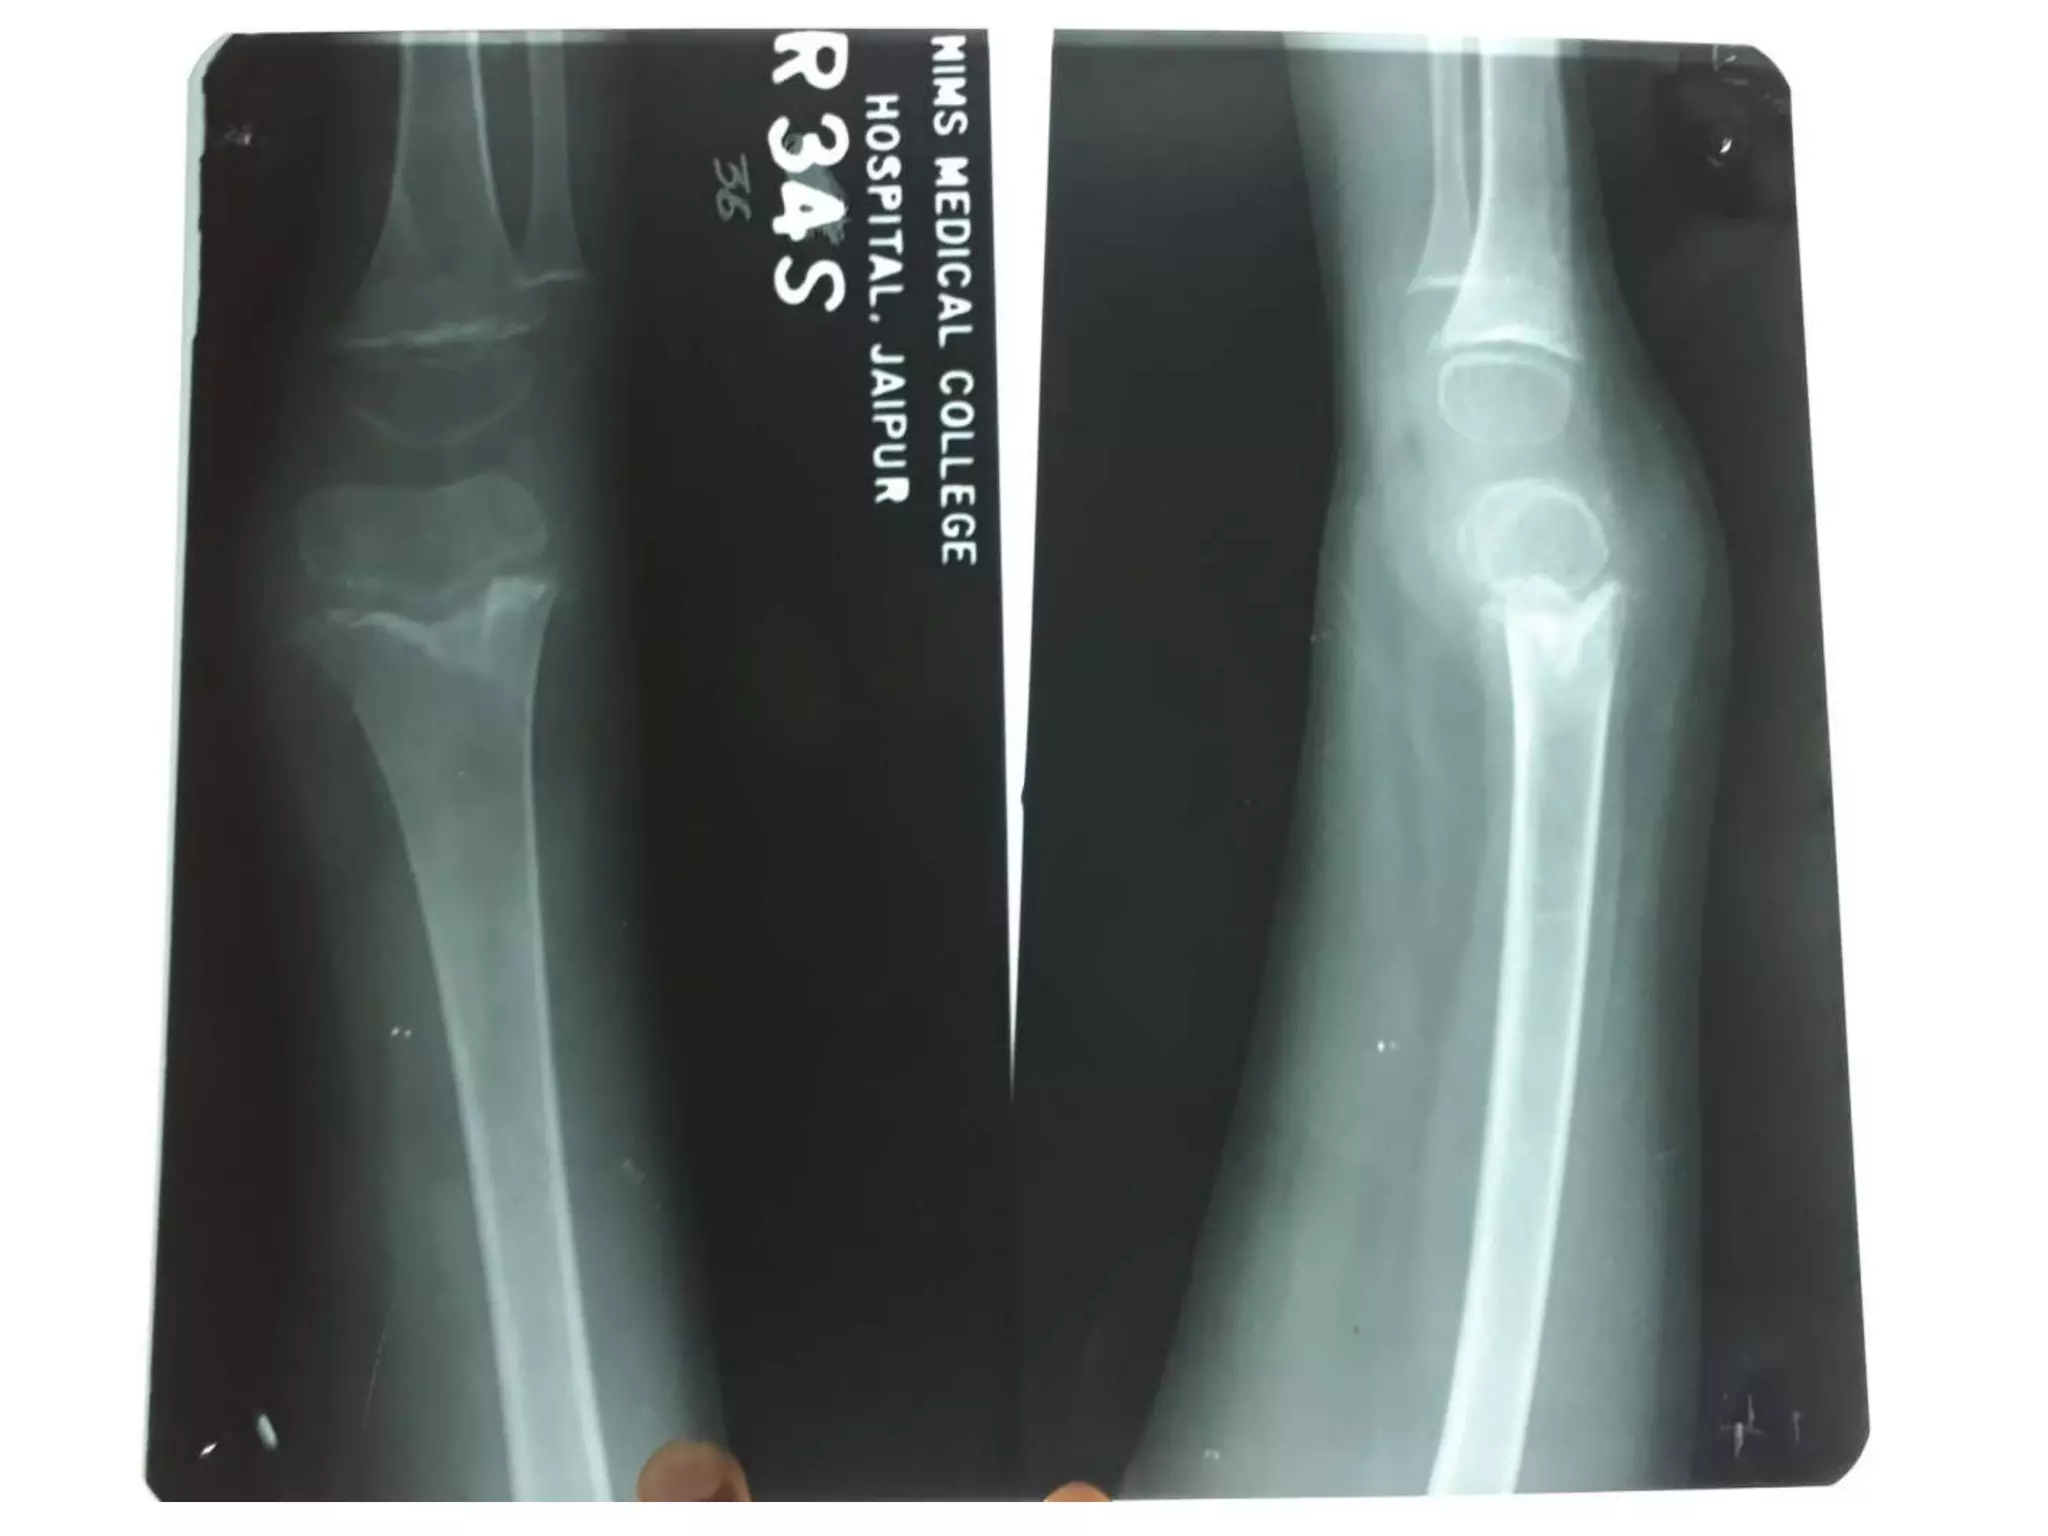

RICKETS

• Demineralization with

coarsening of the

trabecular pattern

• widening of the

epiphysis

• metaphyseal fraying,

cupping and irregularity

at the physeal margin

• Deformity (i.e. bowing)

• flared anterior ribs

RICKETS • Demineralization with coarseningof the trabecular pattern • widening of the epiphysis • metaphyseal fraying, cupping and irregularity at the physeal margin • Deformity (i.e. bowing) • flared anterior ribs